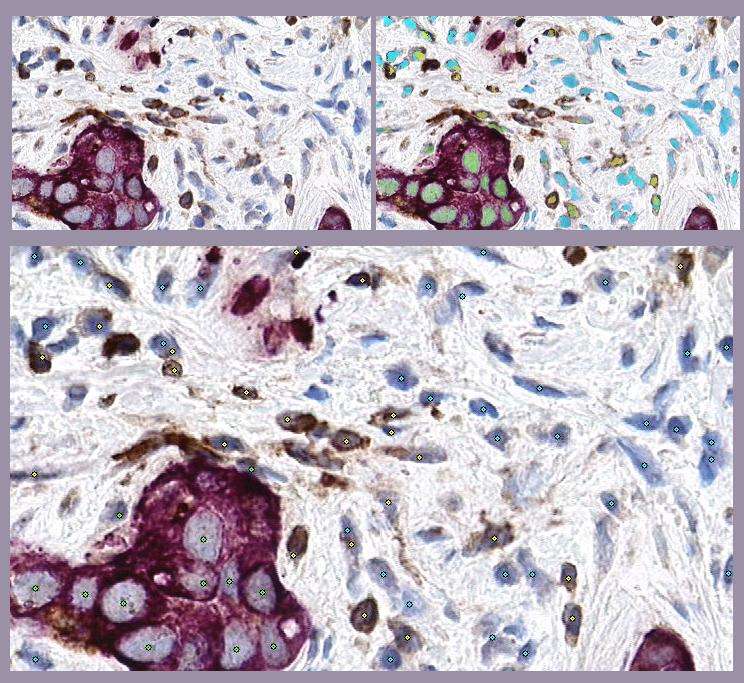

This example illustrates GemIdent's ability to find multiple phenotypes in the same image: the raw microscopic image of a stained lymph node (top left) from the Kohrt study,[2] a superimposed mask showing the pixel classification results (top right), and finally the image marked with the centroids of the objects of interest - the cancer nuclei (in green stars), the T-cells (in yellow stars), and non-specific background nuclei (in cyan stars).